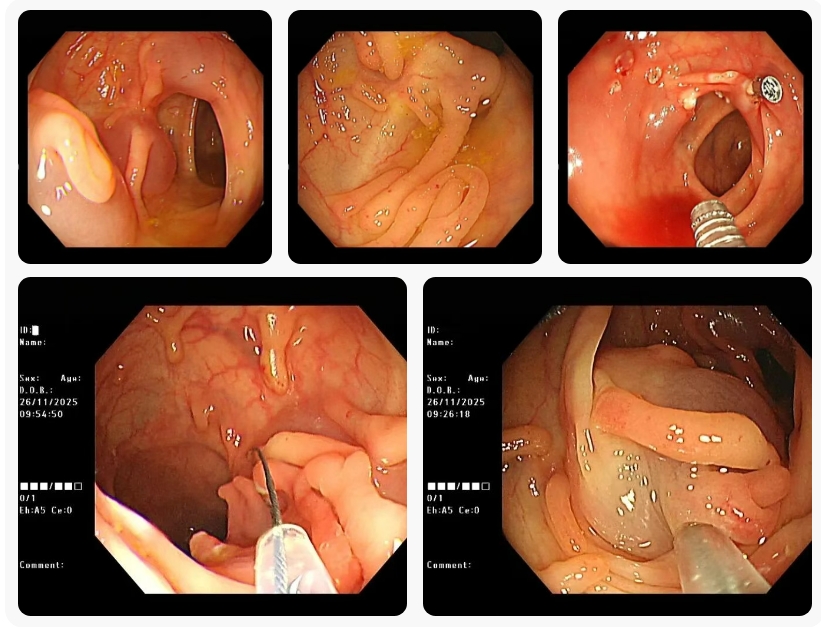

你说多少? 9颗布洛芬? 洛阳白马医院 近日,我院消化内科胃肠镜室接诊了一位特殊患者。小刘因误服9粒布洛芬缓释胶囊,导致药物中毒。所幸,家属察觉异常后迅速将其送至我院就诊。 来院...